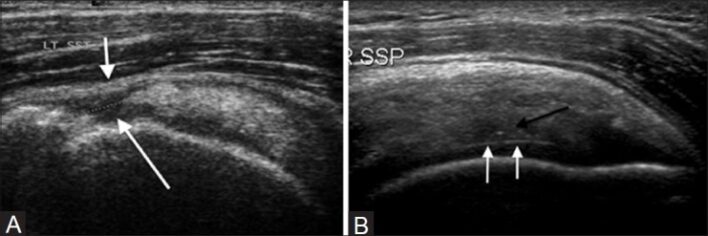

Siêu âm chẩn đoán:

Mục đích chính của siêu âm là nghiên cứu mô mềm. Với người thực hiên giàu kinh nghiệm, siêu âm có độ nhạy 93-100% và độ đặc hiệu 85-97% đối với rách hoàn toàn và độ nhạy 69-93% với rách một phần.

Những kết quả này có thể so sánh ngang với MRI. Bốn tiêu chuẩn của bệnh lý CCX là không nhìn thấy CCX, không nhìn thấy một vùng ( biến mất cục bộ), mất liên tục, và ổ nghèo echo bất thường.